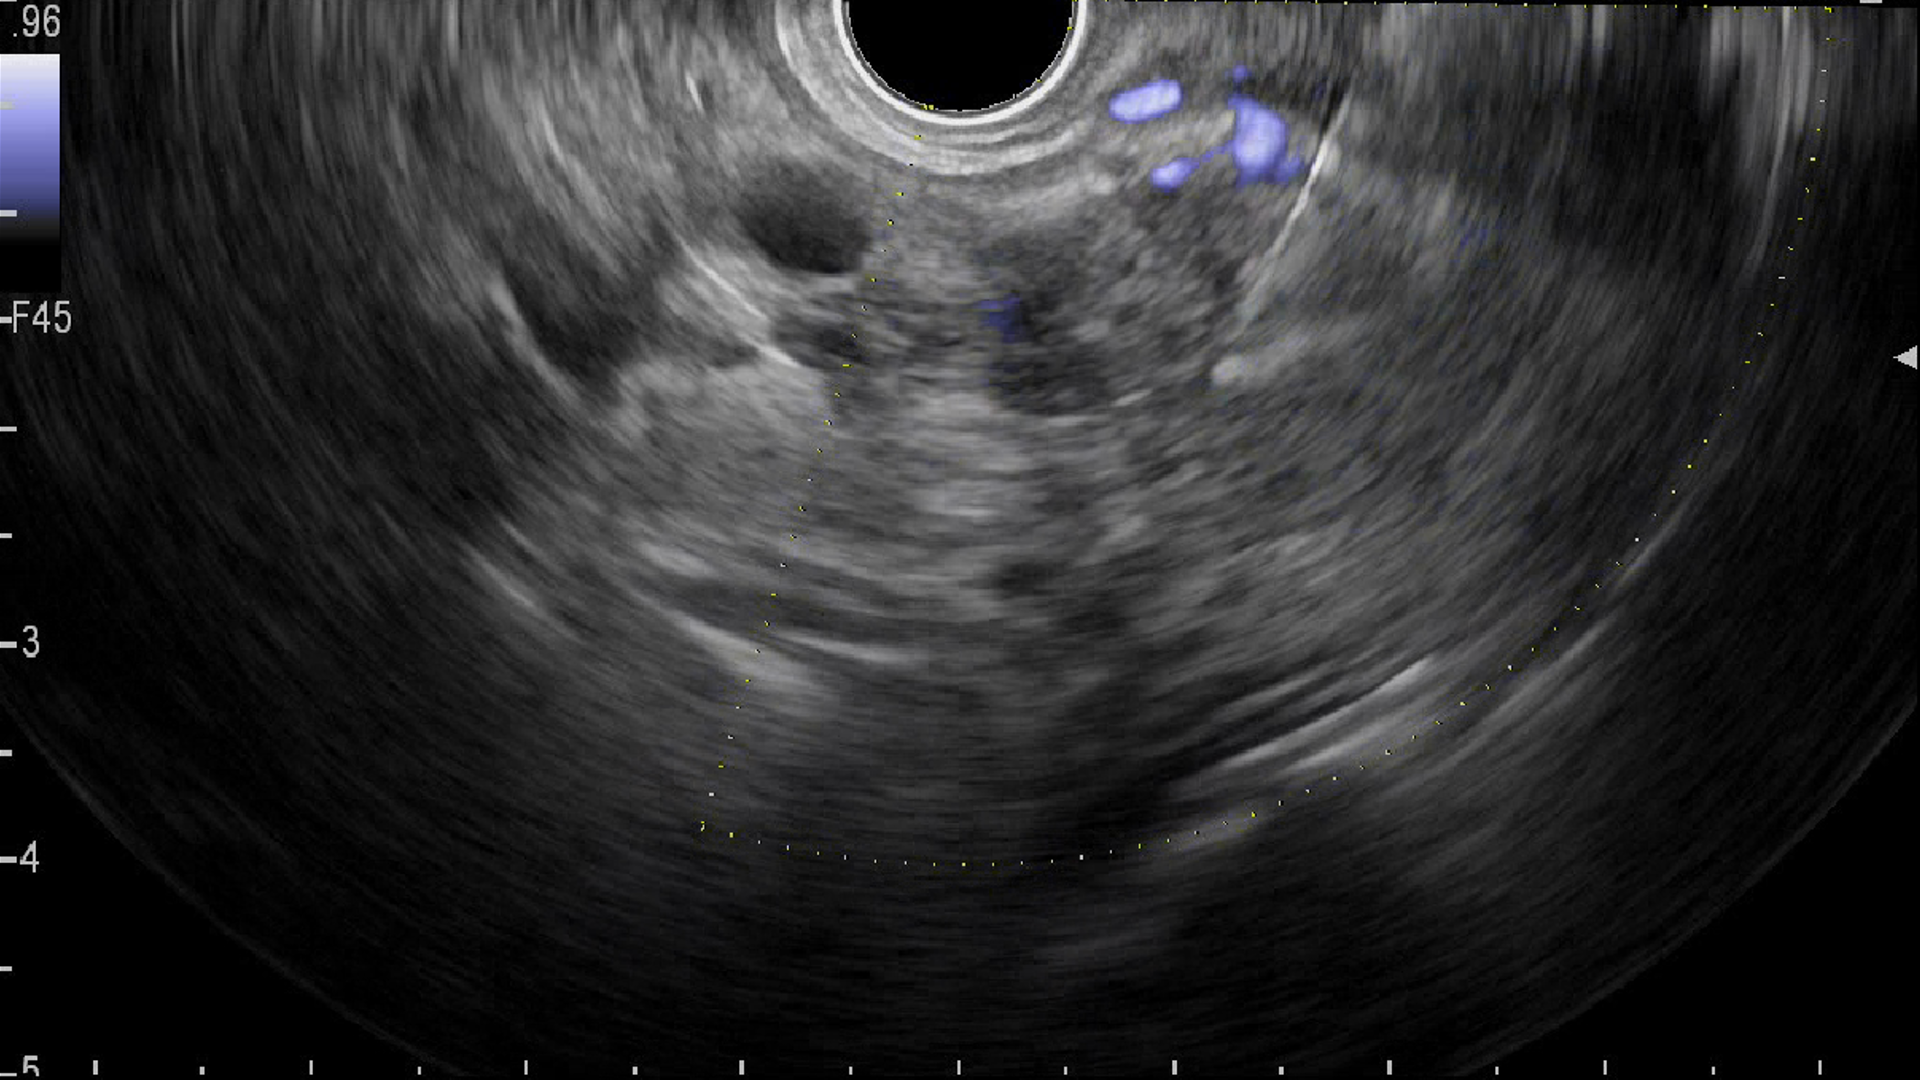

2. ЭУС - контрастное усиление новообразования поджелудочной железы: слабое накопление контраста | |